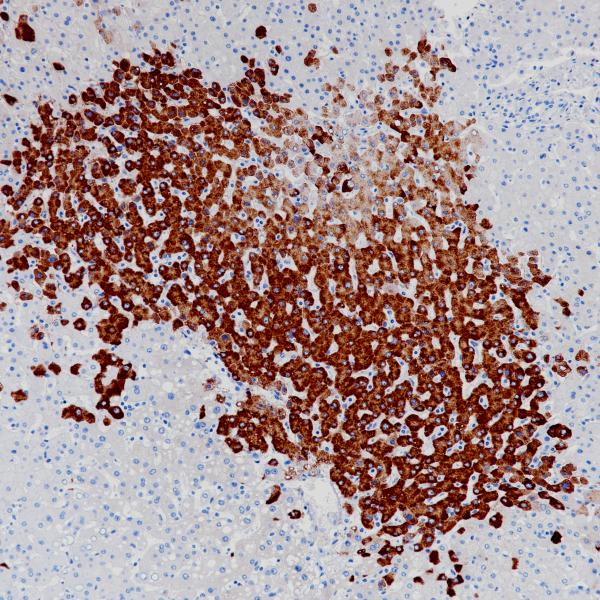

Hepatocyte

OCH1E5